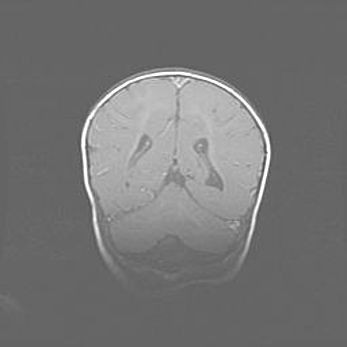

Церебральная ишемия II.

Возраст: 7 дней

Вес: 3350 г

Пол: женский

Окружность головы: 35 см

Срок гестации: 39 недель

Ишемия головного мозга – это состояние, которое развивается в ответ на кислородное голодание вследствие недостаточного мозгового кровообращения. У новорожденных она является следствием дефицита кислорода, что ведет к метаболическим расстройствам различной степени тяжести в тканях головного мозга, в том числе к развитию коагуляционных некрозов и гибели нейронов.